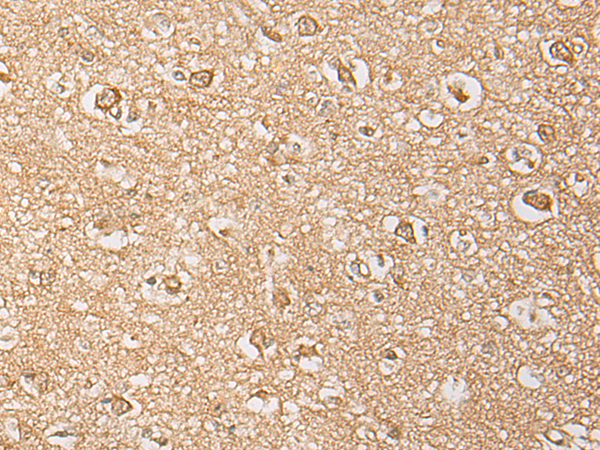

IHC positive control: |

Human brain;Human lung cancer |

IHC Recommend dilution: |

25-100 |